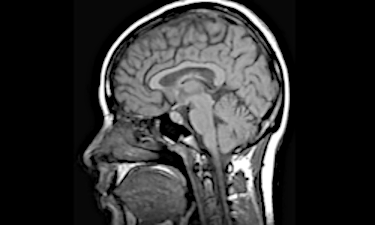

La investigación del grupo IMARD tiene dos objetivos: identificar los cambios en el cerebro implicados en los trastornos del estado de ánimo y de ansiedad, y determinar los mecanismos cerebrales que predicen quién responderá mejor o peor a diferentes tratamientos. Para lograr estos objetivos, el grupo utiliza diversas técnicas de neuroimagen (como la resonancia magnética cerebral), que a menudo se combinan con técnicas de inteligencia artificial.